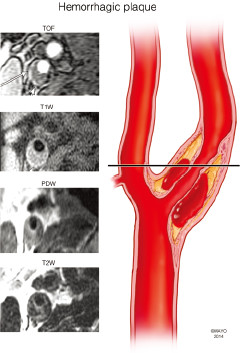

讨论:狭窄率一样,治疗方法就一样吗?

题目:四个患者ABCD去医院体检,都做了超声,发现有颈动脉斑块,且管腔狭窄率基本一样(60%左右),后续又安排做了高分辨核磁,发现A的斑块以钙化为主,B以大脂质核为主,C有斑块内出血,D的斑块已经破裂(如下图所示),ABCD都尚未出现脑缺血症状······

D

4.jpg